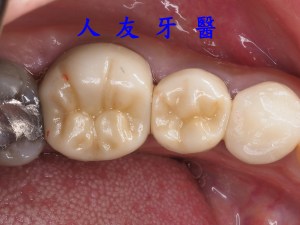

86歲的廖婆婆因為牙齒斷裂深度到達牙根。屬於中度的斷裂程度了,根據斷裂的深度,有可能會部分神經組織會暴露出來。醫師先把裂掉的部分拿掉,試著保留婆婆最多的自然齒質,先幫婆婆做個測試牙套保護觀察是否會疼痛,會痛就需要接受根管治療(抽神經),若不會痛就可直接換正式牙套保護,讓牙齒多一層保護避免二次斷裂。而婆婆在試戴測試牙套的過程中都沒有不舒服的感覺,所以可以保留神經直接換成正式牙套保護。